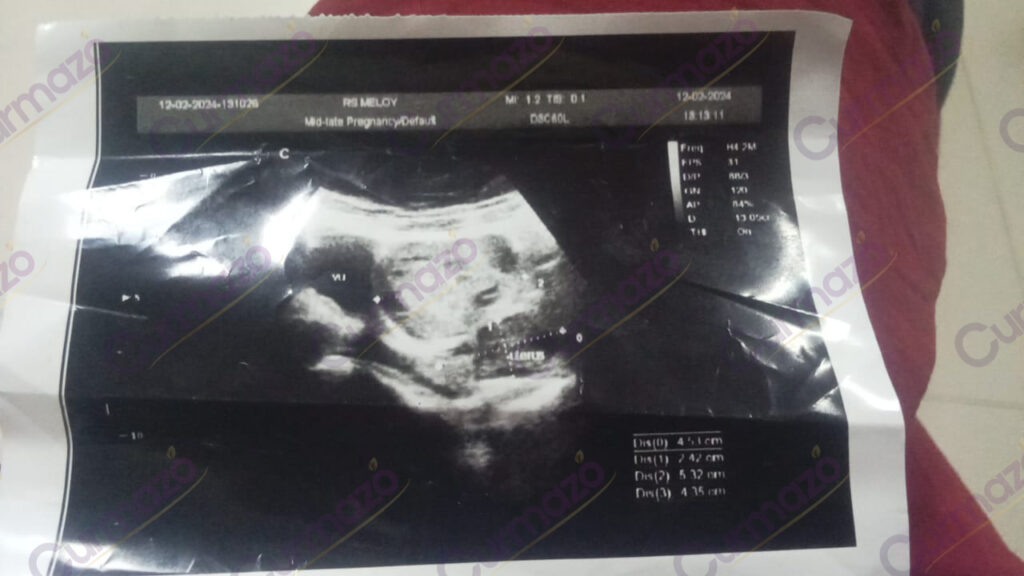

Pada 2 Maret 2024, saya mengalami haid yang berkepanjangan disertai pendarahan, dan sering ingin buang air kecil. Lalu saya periksakan ke dokter, hasilnya ada miom 5.32 cm dan dianjurkan untuk operasi namun saya menolak karena takut.

Hasilnya, setelah 2 bulan pengobatan saya merasa ada perubahan baik di tubuh saya. Siklus haid kembali normal, sudah tidak ada pendarahan, dan perut tidak terasa begah lagi.

2 Mei 2024, saya periksakan kembali hasilnya alhamdulillah miom hilang total. Sekarang saya bisa menjadi istri sekaligus ibu yang sehat & bahagia.